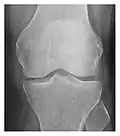

Figure 3: A 26-year-old man presenting with wrist pain after being assaulted. (a) Initial anteroposterior radiograph shows a subtle linear lucency within the scaphoid extending to the scaphocapitate articular surface that was overlooked (arrow). (b) Initial "scaphoid" view was negative. (c) Followup anteroposterior radiographs, 12 days later, shows obvious scaphoid fracture (arrows).[1]

Triquetral fracture usually occurs on the dorsal aspect by impingement from the ulnar styloid or avulsion of strong ligamentous attachment. The dorsal avulsion fracture or "chip fracture" appears as a small bony fragment on the dorsal aspect of the triquetrum and is best detected on the lateral view(Figure 4). When radiography is negative in patients with high suspicion of a fracture, both MRI and MDCT will be of value. However, it has been shown that MRI is superior for detecting trabecular fractures in carpal bones.

a

b

Figure 4: Dorsal triquetral fracture of the left wrist in a 30-year-old man after a trauma. (a) Anteroposterior radiograph shows a normal appearance. (b) Lateral radiograph of the same wrist demonstrates a chip fracture off the dorsal aspect of the triquetrum (arrow).[1]